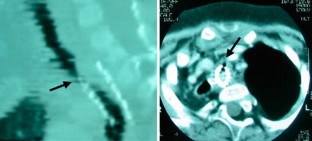

We report a case of tracheal obstruction caused by an expandable metallic stent. A 3-month-old girl with severe tracheomalacia had a placement of a Palmaz stent. At 3 years of age, she developed progressive dyspnea. The CT scan showed tracheal obstruction caused by granulation tissue over the stent. At operation, the stent was found to have penetrated the posterior tracheal wall. Under partial cardiopulmonary bypass, the stent was removed along with the membranous wall of the trachea, and the trachea was reconstructed using slide tracheoplasty. Tracheal obstruction is one of the serious complications caused by an expandable metallic stent. Direct open approach to the trachea under cardiopulmonary bypass is thought to be a safe way to manage this problem.

Fig. 1

Fig. 2